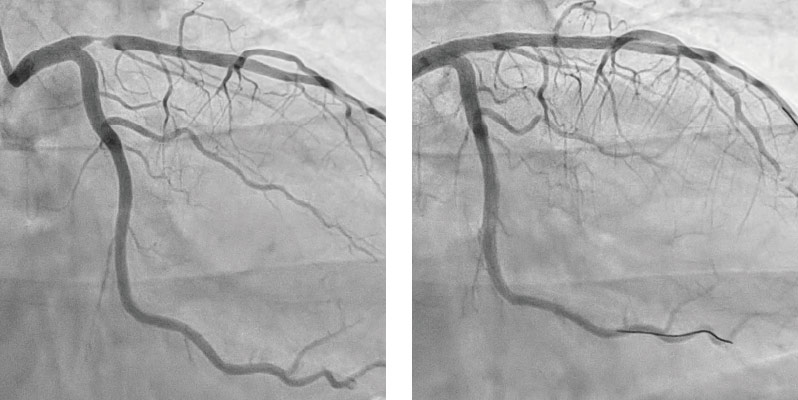

急性心筋梗塞

急性心筋梗塞に対して、緊急で血管治療を行いました。